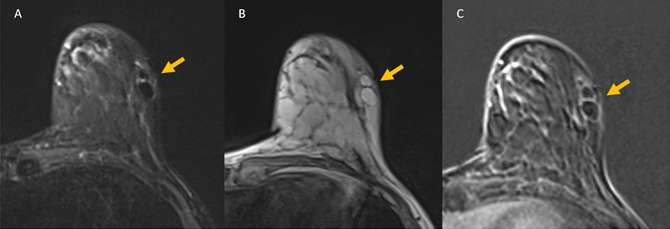

Case: Fat Necrosis of Breast Figure 4

Figure 4: 49 year old female with history of left lumpectomy for breast cancer. (A) MRI STIR axial sequence shows two oval masses in the left lateral breast with central low signal, darker than the surrounding breast fat (orange arrow). This is the “black hole sign” of fat necrosis. (B) MRI T1 axial non-fat saturated sequence shows the same two oval foci with intrinsic T1 hyperintense signal. (C) MRI T1 axial post-contrast fat saturated sequence shows drop out of signal in the oval masses, which follows the signal of the adjacent breast fat. There is faint peripheral enhancement surrounding the foci of fat necrosis; this may represent granulation or fibrotic tissue.